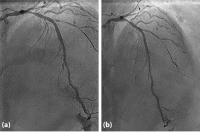

Abbildung

Abbildung 1: The lesion shape before ballooning (a); non-flow limiting dissection after predilatation with NC ballon (b); final result (c)